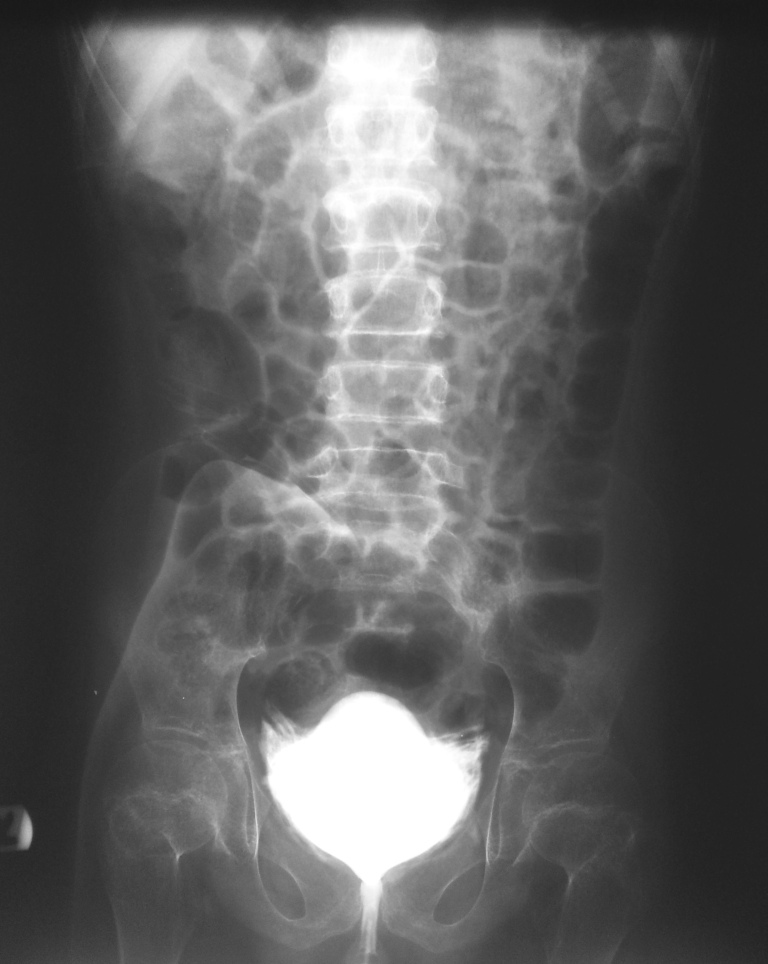

What Type of examination is this?

CT cystogram

Case courtesy of Dr Roberto Schubert, Radiopaedia.org, rID: 14924